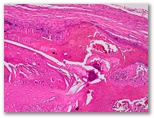

¿dermatofibroma?

Diagnostico